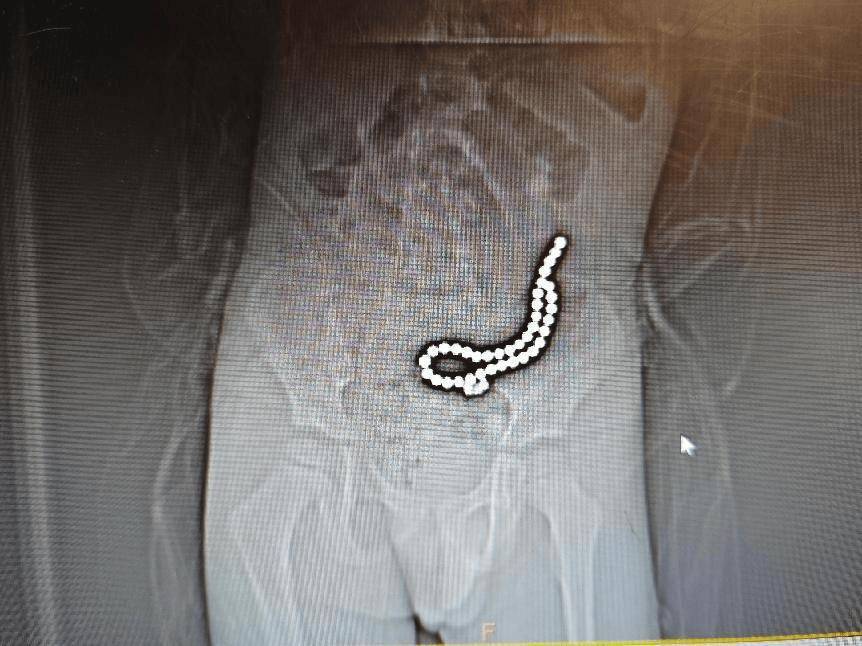

术中取出小肠异物

经过研判,医疗团队凭借着精湛的技术和坚定的信念,克服了重重困难,成功取出了该病人体内的37颗磁力珠,并对穿孔部位进行了细致的修补拜仁慕尼黑足球 。经过数小时的紧张手术,通过腹腔镜、内的联合操作,让病人脱离了生命危险。

术中完善床旁DR见腹腔内已无异物